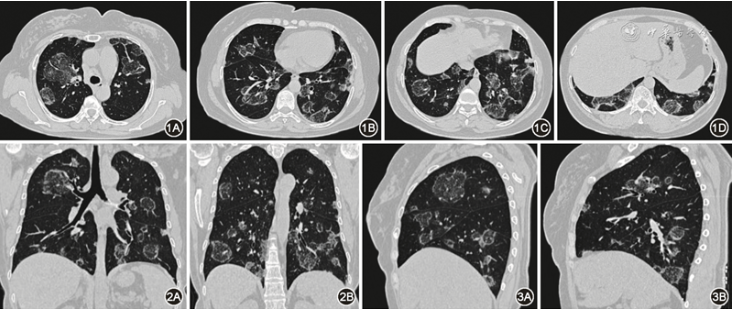

体格检查:体温36.8 ℃,脉率94次/min,呼吸频率23次/min,血压129/88 mmHg(1 mmHg=0.133 kPa)。患者意识清楚,精神状态良好,双肺呼吸音粗,未闻及干湿性啰音,心脏及腹部体格检查未见明显异常,四肢关节无红肿、压痛,双下肢无水肿。入院后完善相关实验室检查,血常规:血小板414×10^9/L(正常参考值为 125×10^9~350×10^9/L);红细胞沉降率为120 mm/1 h(正常参考值为0~20 mm/1 h);风湿指标:C反应蛋白(CRP)15.7 mg/L(正常参考值为0~8 mg/L),抗链球菌溶血素O(ASO)455 U/ml(正常参考值为1~170 U/ml),类风湿因子(RF)499.6 U/ml(正常参考值为1~30 U/ml),抗环瓜氨酸肽(CCP)抗体测定1434 U/ml(正常参考值为0~46 U/ml);抗核抗体谱:抗SSA/Ro抗体>500 U/ml,抗SSB抗体>500 U/ml,抗核抗体1∶100、1∶320、1∶640、1∶1 000均为阳性;肌炎抗体谱:抗Ro-52抗体+++,抗TIF1-γ抗体、抗NXP2抗体、抗Mi-2α抗体、抗OJ抗体、抗MDA5抗体等均为阴性,肌电图:上下肢肌肉无神经传导异常及肌源性损害。肺部肿瘤标志物、结核感染T细胞检测、真菌D-葡聚糖、半乳甘露聚糖、抗中性粒细胞胞质抗体、痰细菌培养、抗酸杆菌涂片、真菌涂片均为阴性;2024-01-12胸部HRCT:双肺多发大小不等团片状、结节状密度增高影,呈反晕征象(图1, 图2, 图3)。

图1 2024年1月12日胸部HRCT(轴位)肺窗示双肺散在分布大小不等的斑片状、结节状密度增高影,中央为磨玻璃密度,外周边缘为环状高密度影,呈反晕征像,部分结节内可见血管穿行影

图2 2024年1月12日胸部HRCT(冠状位)肺窗示双肺以中下肺野为主的多发斑片状、结节状反晕征影,部分病灶周围可见条索状密度增高影

图3 2024年1月12日胸部HRCT(矢状位)肺窗示双肺内病灶呈反晕征影,部分小结节呈混合磨玻璃样密度增高影